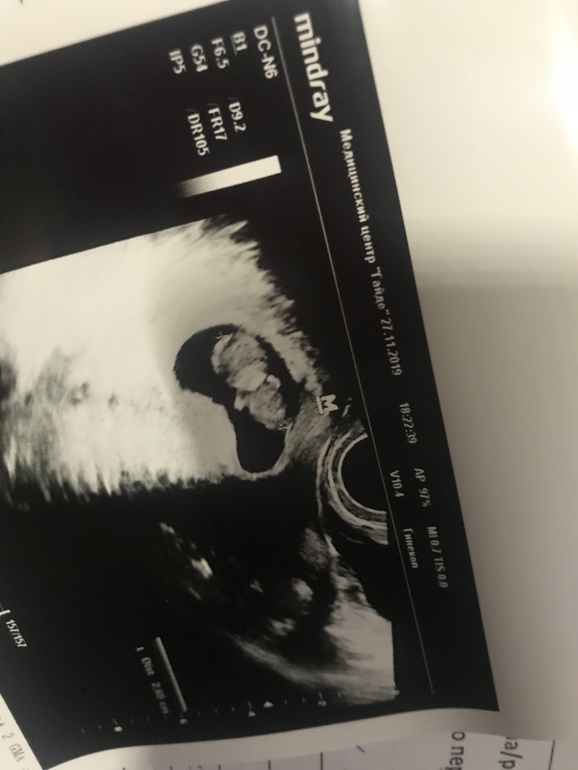

Была сегодня на платном узи 👇

КТР - 26 мм (выросли за две недели на 16 мм)

Желт. мешочек - 5 мм

С/б - 166 ударов в минуту 💓

Вначале мы спали, положив голову на грудь 😄👇